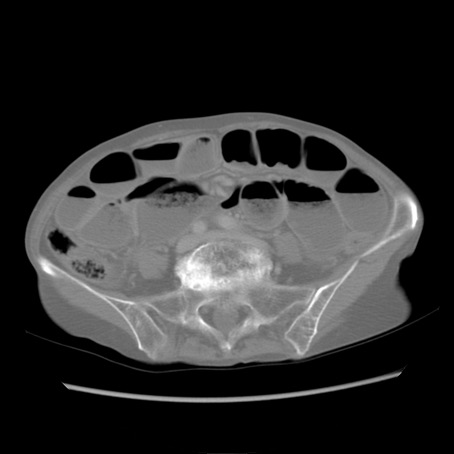

症例25(横断像)

【症例】80歳代女性

【主訴】胸のつかえ感

【現病歴】約9時間前に食後から胸のつかえた感じあり、嘔吐あり、来院。

【既往歴】胃癌(全摘)、胆摘、虫垂炎

【身体所見】心窩部に圧痛あり、反跳痛なし。

【データ】WBC 5700、CRP 0.05